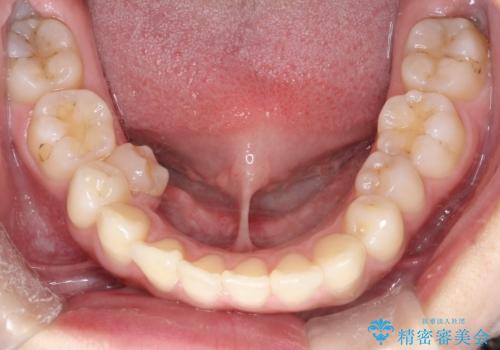

- 前歯の凸凹を主訴に来院されました。

スペースを作るために顎間ゴムを使用して、奥歯の遠心移動をおこない配列しました。

奥歯の遠心移動を行うことで、犬歯関係も良い状態に仕上げることができました。